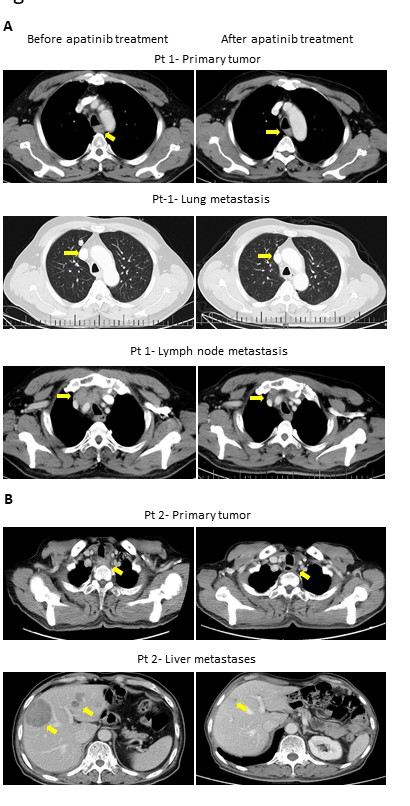

Of the 25 evaluable patients, PR was observed in 3 patients (12%) and SD was observed in 12 patients (48%). No patients met CR. Ten patients (40%) experienced disease progression. The overall response rate (ORR) and disease control rate (DCR) was 12% and 60%, respectively (Table 3). The median PFS of all 26 patients was 3.2 months (95% CI, 2.23-4.17 months) (Figure 3) and OS was 5.3 months (95% CI, 4.46-6.14 months) (Figure 4). We noted that the metastatic tumors were well responsive to the apatinib treatment in the 15 patients with PR or SD. As shown in (Figure 5), metastatic tumors in lung and lymph nodes of one patient were ~50% reduced after one cycle apatinib treatment; in another patient, apatinib killed ~80% liver metastatic tumors. Even in the patients who experienced tumor progression for their primary ESCCs, 8 of the 10 patients showed mild shrinkage or no-change for the metastatic tumors after the apatinib treatment.

Figure 5: CT images of two ESCC patients with lung and lymph node metastasis (Pt 1, A) and liver metastasis (Pt 2, B).